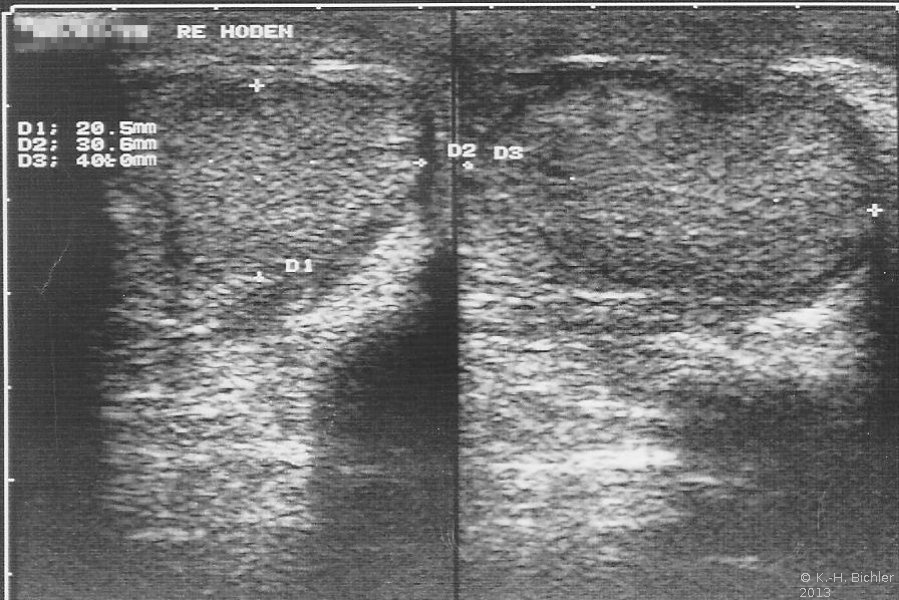

Das Beispiel zeigt die Situation bei einem 25 Jahre alten Mann, der phänotypisch normal männlich war. Bei der Untersuchung war der rechte Hoden tastbar und sonographisch nachweisbar (Abbildung 2).

Links kein Hoden palpabel. Verdacht auf Hodendeszensusstörung. Wegen einer rechtsseitigen Hernie wurde die Leiste von einem Inguinalschnitt aus freigelegt. Dabei fanden sich zwei Hoden verbacken mit einem rudimentären Uterus, tubulären Strukturen und einem Vaginalstrang (Abbildung 3). Der kleinere Hoden sowie die Müller-Gang-Derivate wurden entfernt.